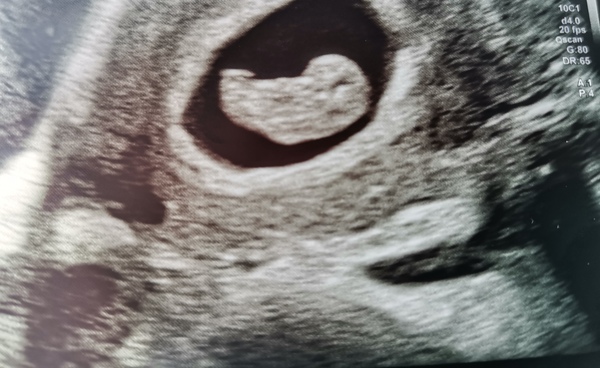

I had a scan over a week ago at 9 weeks and it's already grown so much from my 6 week scan....😍